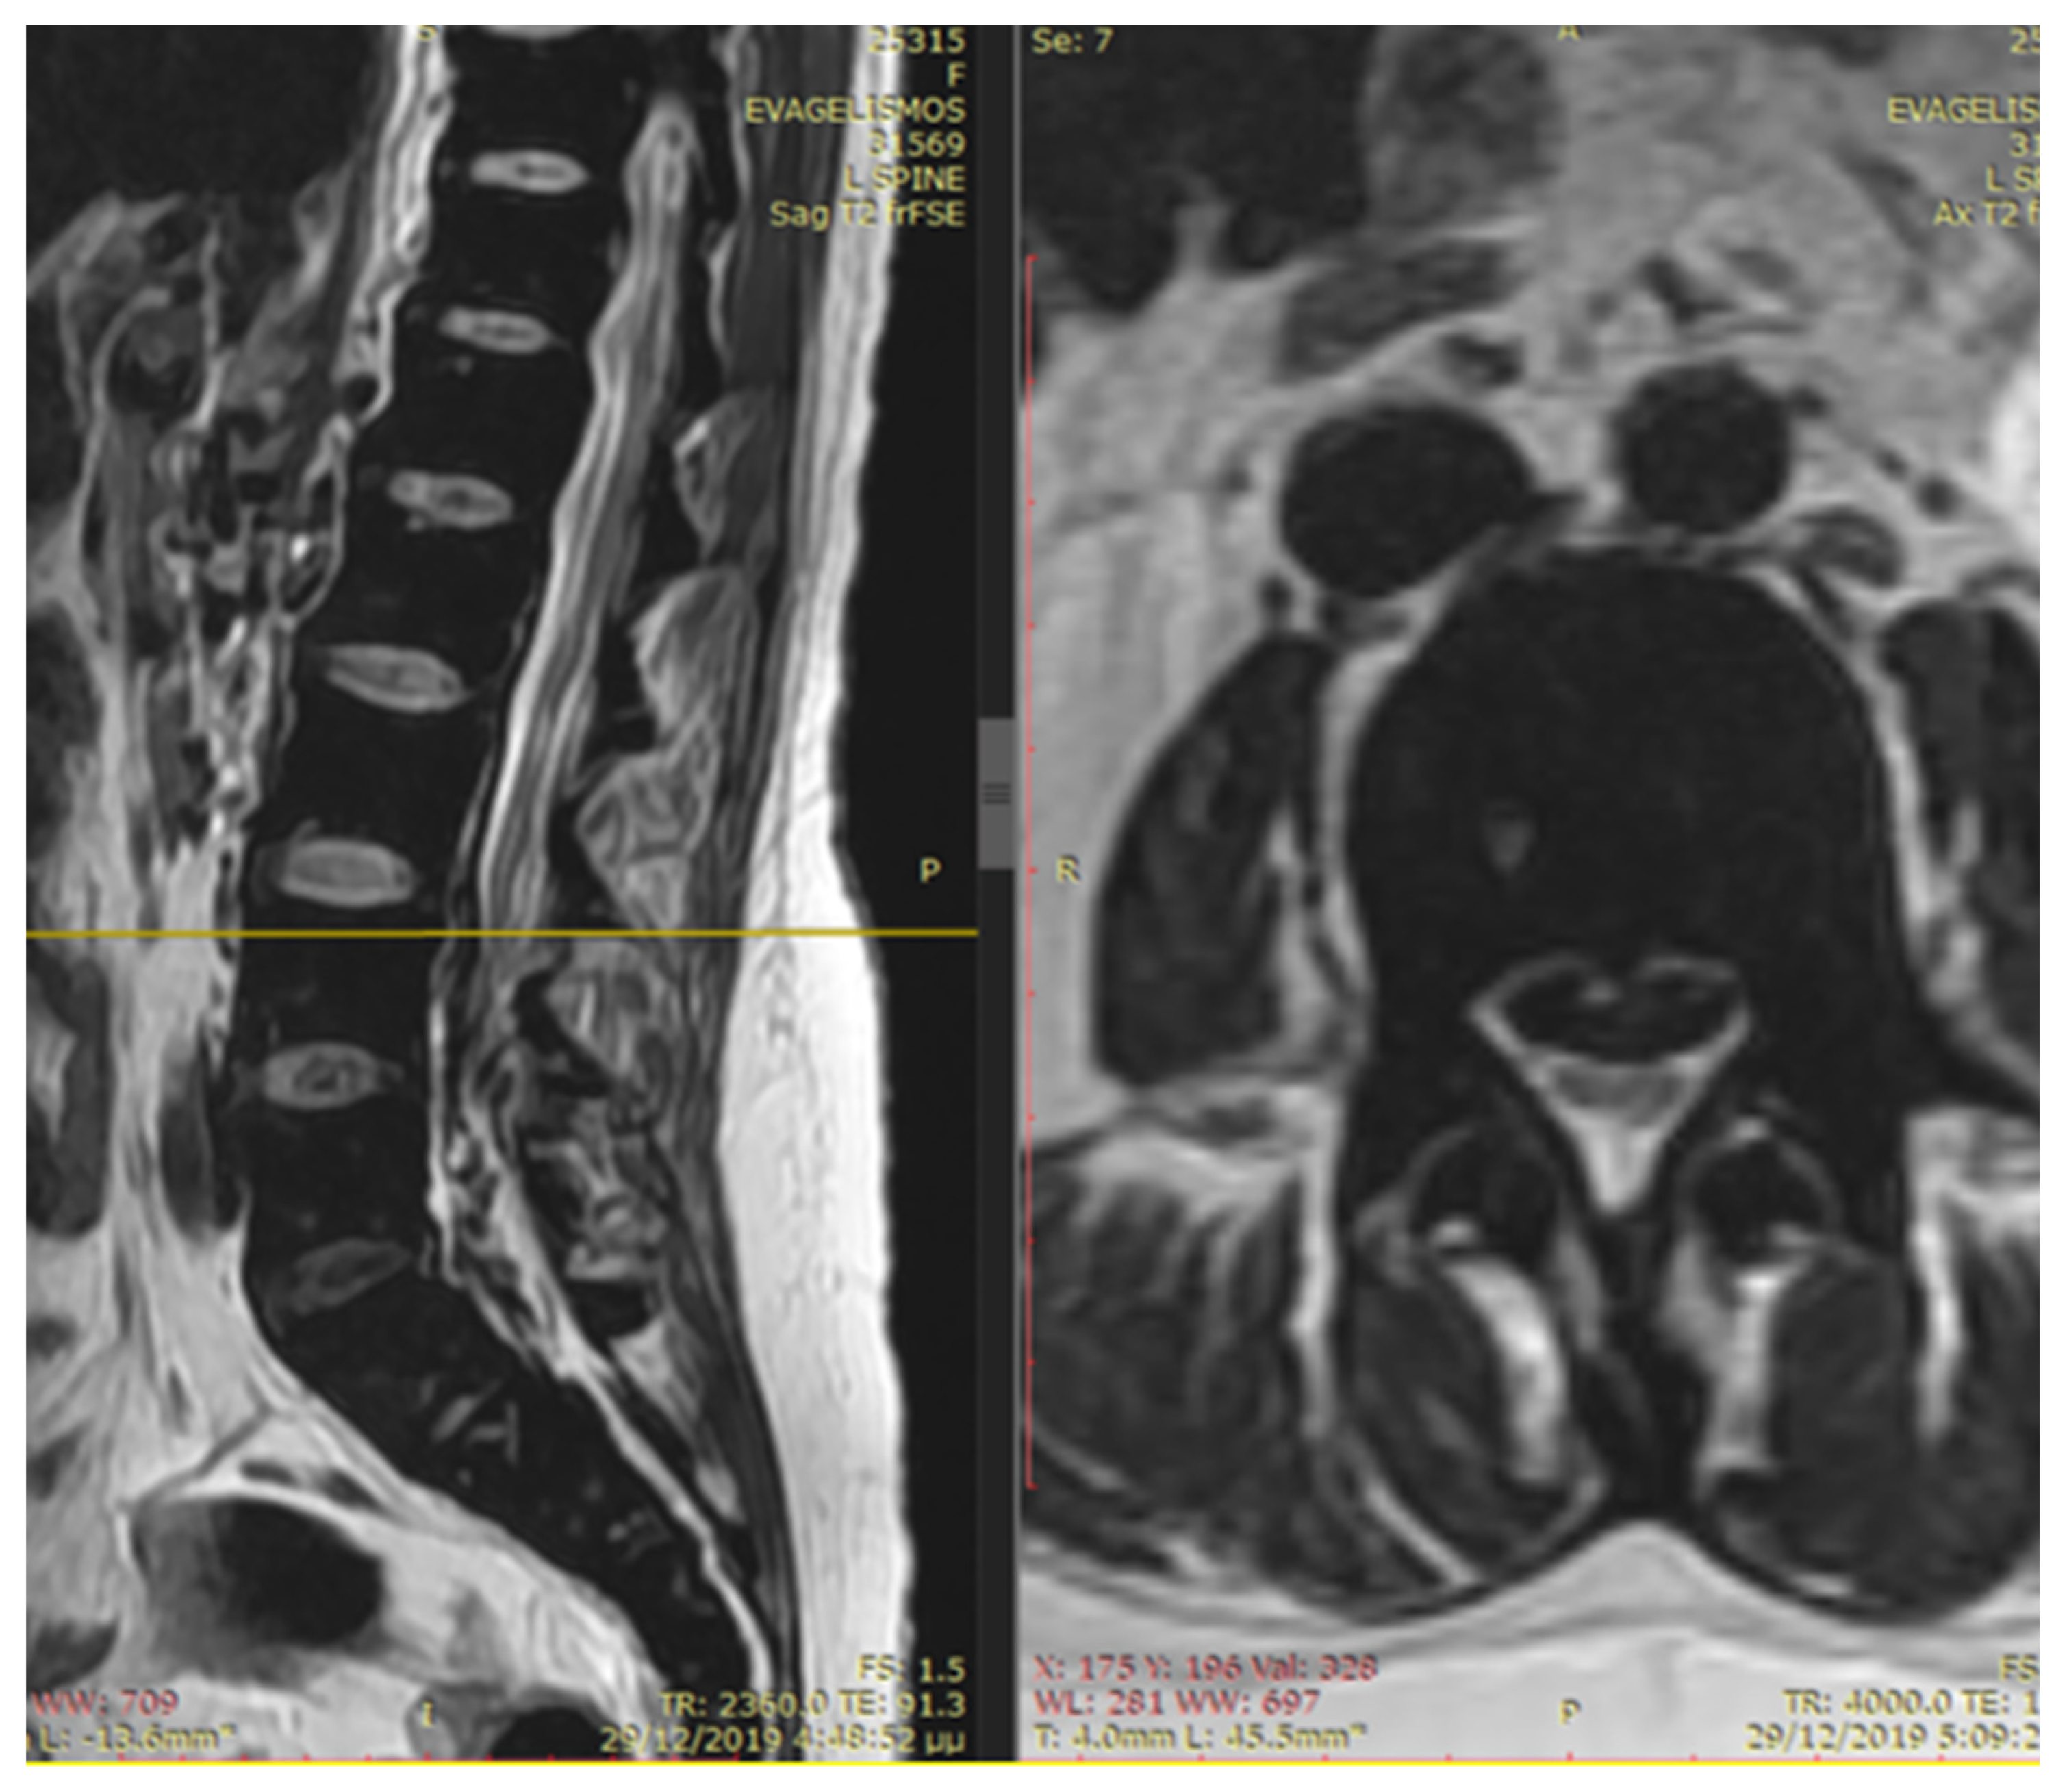

An emergency MRI was conducted on the patient, and the findings can be succinctly summarized as follows. In the T2 sequence, a low signal is observed in the anterior epidural space, accompanied by an uneven signal in the T1 sequence. These observations indicate compressive effects on the dura at the level of L2, extending towards the posterior segments of the spinal canal up to the final segment. Furthermore, a portion of this compression appears to extend along the midline fissures on the right side, particularly at the levels of L5–S1 and S1–S2, causing mild compressive effects on the nerve roots. In the GRE sequence, a low signal is noted in a segment of the aforementioned distribution, raising strong suspicion of hemosiderin deposition (Figure 1 and Figure 2). In the fat-suppressed T2 sequence, there is a diffuse increase in signal, signifying edema, in the soft tissues at the level of the midline fissures in the posterior elements and the soft tissues between the ligamentum flavum and the dura at the intervertebral foramina level. Additionally, edema is observed in the epidural space.

Figure 1.

In the T2 sequence, there is a low signal in the anterior epidural space, along with an inhomogeneous signal in the T1 sequence. These findings suggest compressive effects on the dura at the level of L2, extending to the posterior parts of the spinal canal until the final segment. Additionally, a segment of this compression seems to extend along the course of the midline fissures on the right side, specifically at the levels of L5–S1 and S1–S2, causing mild compressive effects on the nerve roots.